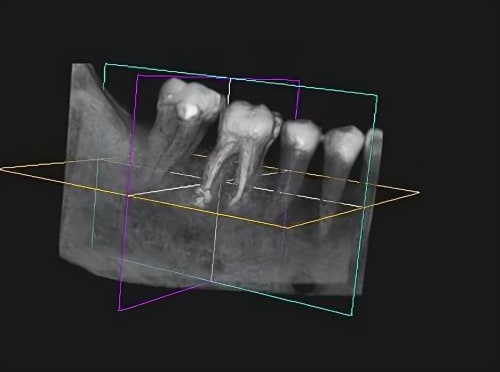

Um eine schonende operative Zahnentfernung durchzuführen, ist eine ausführliche Diagnostik im Vorfeld notwendig. Dazu können dreidimensionale Röntgenaufnahmen, sogenannte DVT-Aufnahmen, verwendet werden. Diese ermöglichen eine präzise Behandlungsplanung und ein schonendes Vorgehen.

1. Strahlungsarme DVT (Digitale Volumentomografie): Durch diese fortschrittliche Technik können detaillierte und dreidimensionale Bilder von Zähnen, Kieferknochen und umgebenden Strukturen erzeugt werden, die eine exakte Diagnose ermöglichen und die Planung von schweren Eingriffen erleichtern.